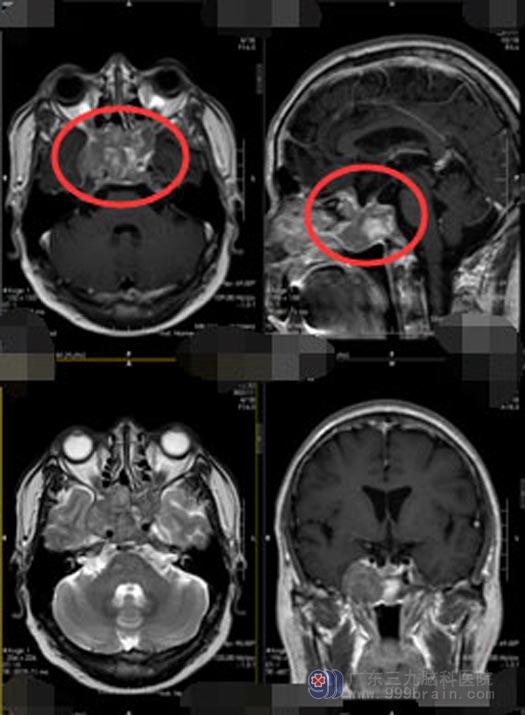

一个月前,肖先生又开始头痛,并且越来越严重,在当地医院检查发现鞍区有占位,医生考虑是肿瘤复发。肖先生及家人觉得这次治疗得找一家专业性强的医院了,经过多方打听,他们来到了广东三九脑科医院神经外五科。

结合肖先生的病史,经过进一步的检查,神经外五科的医生也考虑是肿瘤复发。由于各地医疗水平不同,肿瘤性质、质地各异,再加上术后缺乏规律随访等等,部分垂体瘤没有得到有效切除,导致术后肿瘤复发。

经患者及家属同意后,神经外五科手术团队为肖先生实施“神经内镜下经鼻蝶鞍区占位切除术”,术中发现肿瘤主要在蝶窦和筛窦,并突入右侧海绵窦内,海绵窦内的残余肿瘤导致的垂体瘤复发。手术顺利,术后病理显示为垂体腺瘤。术后,肖先生头痛症状明显改善,无脑脊液鼻漏,无发热,无鼻腔流血,已满意出院。